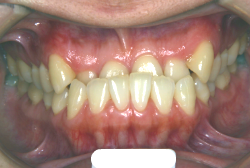

叢生(そうせい)

凸凹な歯並びのことを叢生といいます。矯正歯科に来院する患者様の主訴の中で、最も多いのが「配列の凸凹を真っ直ぐにしたい」というものです。歯の大きさと顎の大きさの調和がとれていないことが原因です。

凸凹を主体としたケースの場合、当院の平均治療期間は18ヶ月ですので、このケースは少し長めに経過しました。理由の一つは凸凹の程度がかなり重症だったと言うことですが、もう一つは、右下第2大臼歯が45度くらい前傾していたため、それを整直化させるために時間を要したと考えています。いずれにしても最終結果は大変よい状態と思います。

治療前は並びが乱れて見た目が悪いというのはもちろん問題ですが、歯科医学的に一番困るのは噛み合わせが悪いという点です。上下の犬歯(3番目の歯)は、上下的に離れた位置にあるため接触することができません。つまり歯としては存在していても、歯としては機能していないということです。